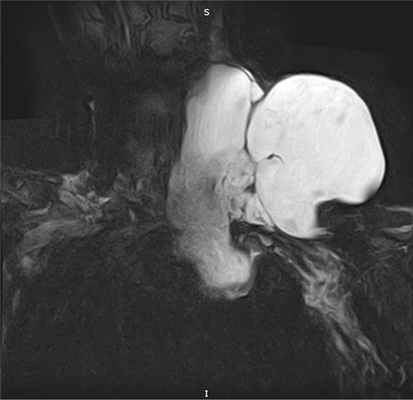

При МРТ мягких тканей шеи (рис. 2) Рис. 2. МРТ-картина мягких тканей шеи. Двухкамерное кистозное образование шеи с медиастинальным компонентом. в левой надключичной области по боковой поверхности шеи слева, вдоль сосудистого пучка, с распространением в верхнее средостение до уровня легочного ствола и по ходу плечеголовной вены слева в область плечевого сплетения определяется объемное двухкамерное образование с четкими границами общим размером 174×150×190 мм. Образование прилежит к основным магистральным сосудам шеи и средостения, без признаков инвазии, контактной костной деструкции и без инфильтрации окружающих мягких тканей. При внутривенном контрастировании отмечается накопление контрастного препарата стенками выявленной структуры и септами внутри полостей. КТ органов грудной клетки: образование распространяется в подчелюстную область слева в грудную полость до уровня дуги аорты. При ультразвуковом ангиосканировании вен диагностирован окклюзивный тромбоз левой подмышечной вены. На фоне антикоагулянтной терапии через 1 мес отмечены признаки частичной реканализации.